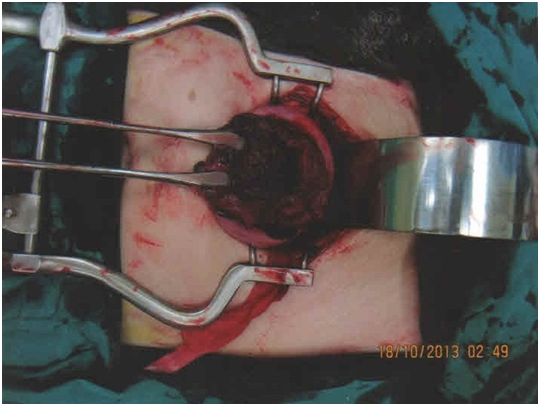

Under general anaesthesia, emergency laparotomy was performed via a pfannenstiel incision. 1.7 liters of hemoperitoneum, mostly in clots, was evacuated. The intra-operative finding was that of the fetus intact in the amniotic sac free floating in the peritoneal cavity (Figure 3). The rupture site was identified and found to be located at the fundus of the uterus (Figure 4). The placenta was found to be located fundally, at the site of the uterine rupture. There was no other significant abnormality or deformity of the uterus. Bilateral fallopian tubes and ovaries appeared healthy and normal. The gestation sac, fetus and plcaenta were removed and blunt curettage of the cavity was performed. The uterine defect was closed with 0 polyglactin 910 (VicylTM) sutures in 2 layers. The fetus weighed 224g and the placenta weighed 110g. The placenta was sent to the pathology lab for histological examination. A total of 5 units of packed red blood cell and 2 units of fresh frozen plasma were transfused. The patient was monitored in the intensive care unit for 12 hours and the high dependency unit for the next 48 hours. She was discharged home well on the 5th post-operative day.

Figure 3 Fetus in amniotic sac free floating in peritoneal cavity encountered during emergency laparotomy.